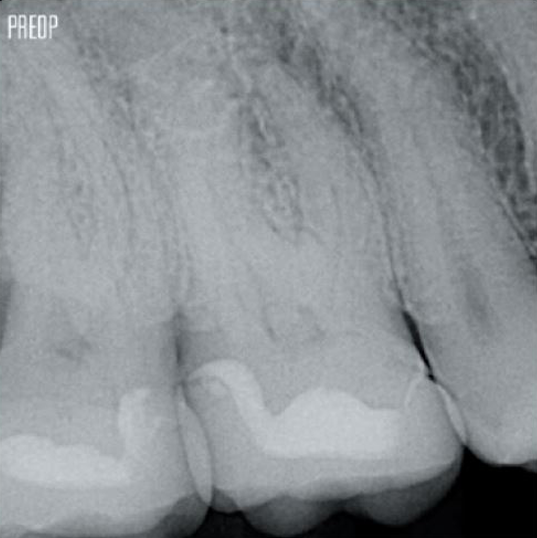

Foto's met dank aan dr. Ahmed Salman

Een geslaagde wortelkanaalbehandeling begint met goede toegang tot de pulpakamer. De ideale ingreep biedt toegang tot wortelkanaalopeningen met minimaal verlies van dentine.

Een conservatieve endodontische caviteit (CEC) wordt aanbevolen bij gebruik van het TruNatomy®-systeem.

De combinatie van de vijlgeometrie, regressieve tapsheid en de slanke, zeer flexibele draad maakt een efficiënte wortelkanaalbehandeling mogelijk, waarbij alleen dentine wordt verwijderd waar dat klinisch noodzakelijk is.1